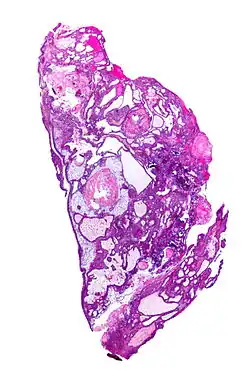

On macroscopic examination, craniopharyngiomas are cystic or partially cystic with solid areas. On light microscopy, the cysts are seen to be lined by stratified squamous epithelium. Keratin pearls may also be seen. The cysts are usually filled with a yellow, viscous fluid rich in cholesterol crystals. Of a long list of possible symptoms, the most common presentations include headaches, growth failure, and bitemporal hemianopsia.

Micrograph showing the characteristic features of an adamantinomatous craniopharyngioma - cystic spaces, calcifications, and "wet" keratin, HPS stain -

Micrograph showing a papillary craniopharyngioma, HPS stain